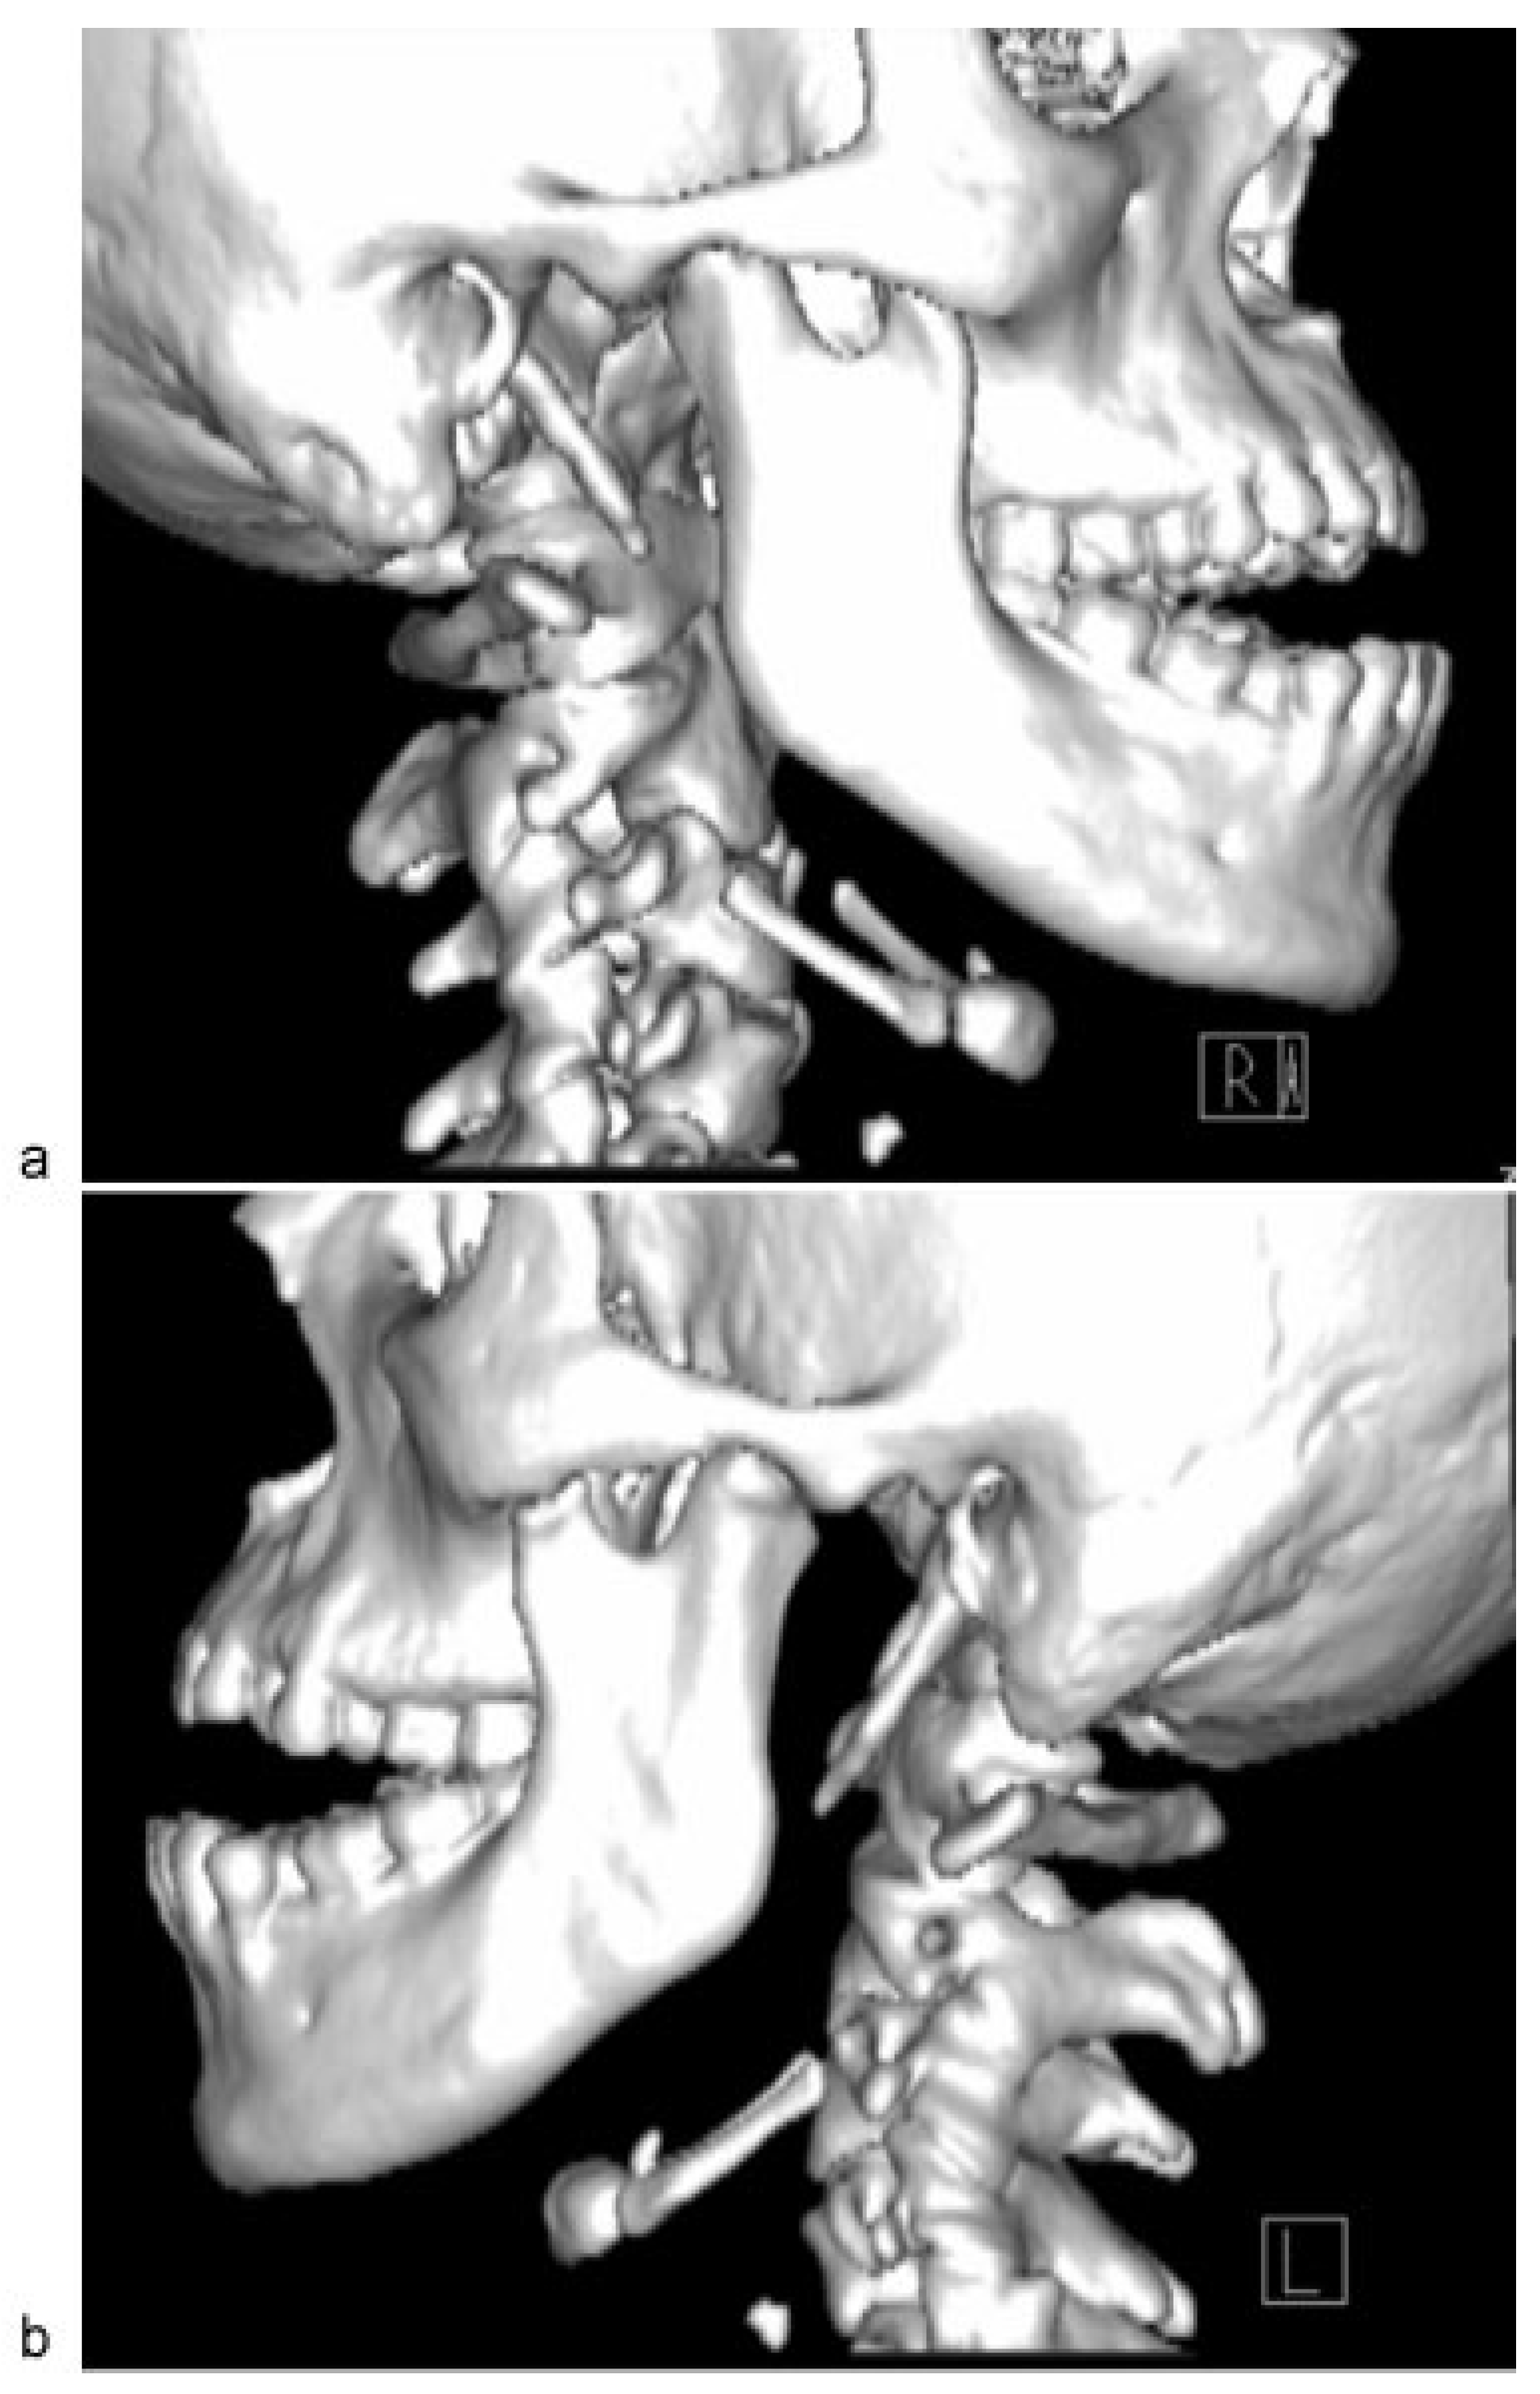

Figure 2]). Closed reduction of the TMJ was attempted for a few times; however, it was unsuccessful because of the stiffness of muscle of mastication.

Figure 2.

Dislocations of right and left condylar heads into infratemporal fossa.

Figure 2.

Dislocations of right and left condylar heads into infratemporal fossa.